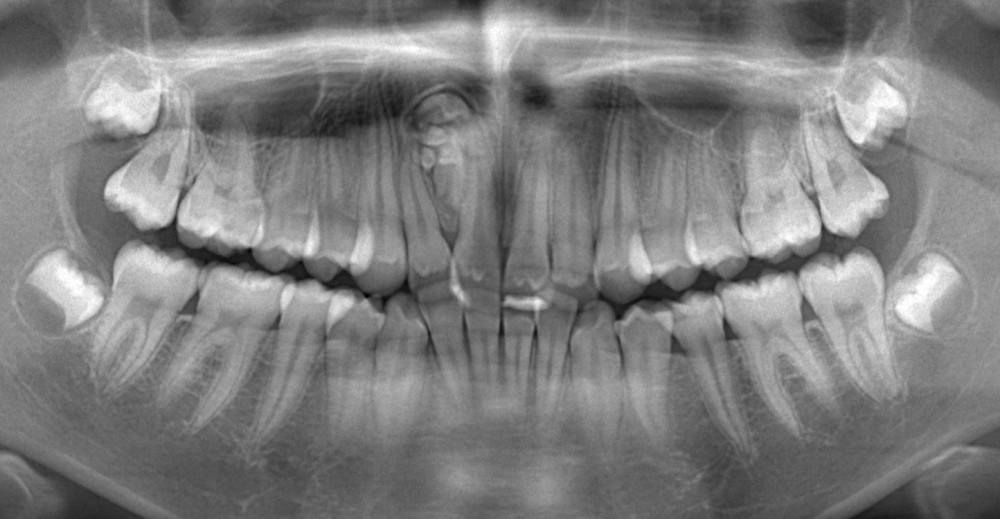

Que voyez-vous sur les coupes du CBCT présentées aux figures 2 à 6 ?

Les images CBCT mettent en évidence une lésion radio-opaque bien circonscrite au niveau antérieur maxillaire, constituée de multiples petites structures calcifiées à morphologie « dentaire ». L’aspect en amas de « micro-dents »…